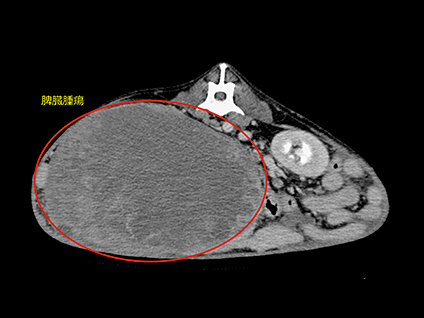

腫瘍性疾患におけるCT検査

腫瘍性疾患のCT検査は、病変の位置や浸潤、転移の有無など、手術前の検査としての役割や、抗癌剤などの治療効果判定としての役割があります。病変部やその周囲を細かく立体的にイメージできるようになるため、「より安全な手術、癌の早期発見」につなげる事ができます。